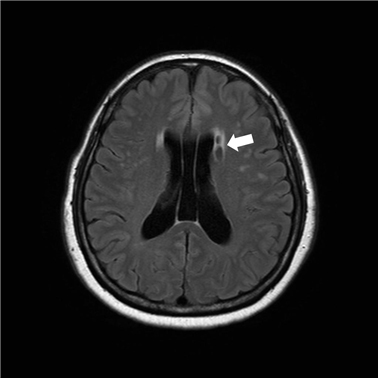

이 질병을 진단하는 검사로는 몇 가지가 이어질 수 있답니다. 뇌졸중에는 뇌출혈과 뇌경색이 있는데, 이 양쪽 모두는 양상이 다르며 무엇이냐에 따라서 치료 절차도 상이하기 때문에 뇌경색 검사방법으로 진단을 정확하게 받는 것이 선행되어야 하고 중요한 부분이라고 할 수 있어요. 우선 뇌경색 초기증상이 보인다면 방문을 하여서 전문가와 상담을 진행하게 되겠고, 진행되는 뇌경색 검사방법으로는 뇌혈관 자기 공명영상, 공명영상 촬영술, 전산화 단층 촬영, 심장 초음파, 경동맥 초음파, 뇌혈관 초음파 등의 방식으로 환자의 현재 상태를 파악하여 치료가 진행되겠죠.